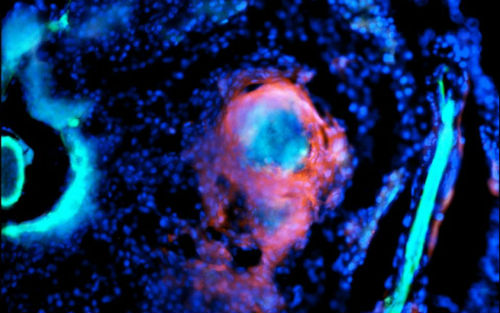

由于在成年期出现条纹前斑马鱼都是透明的,Oehlers可以用不同颜色的荧光标记来标记出细菌、免疫细胞和血管,然后随时间追踪结核感染。当他用亮蓝色的海鱼分枝杆菌来感染斑马鱼时,他看到亮红色的免疫细胞很快包围细菌形成了紧密组织化的肉芽肿。在数天内,在这些小细胞球内部和周围就可看到萌芽的亮绿色血管。他们发现这些新血管是一些功能性的血管,以与正常血管相同的方式运送红细胞。